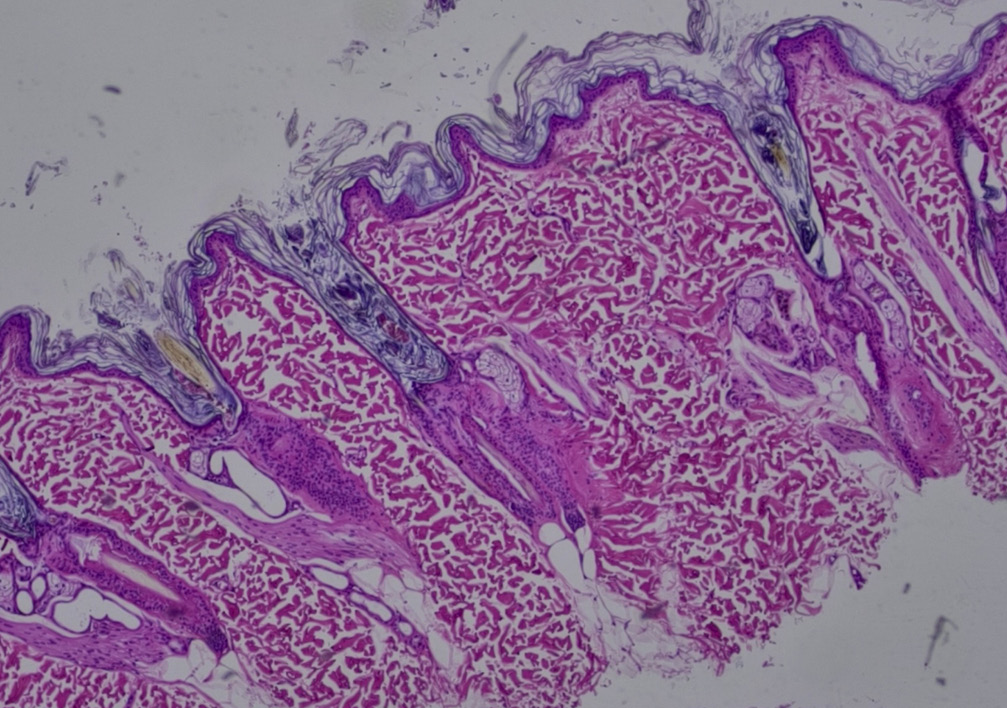

Si, tras estas pruebas iniciales, la sospecha de alopecia X se mantiene, puede plantearse la realización de biopsias cutáneas para estudio histopatológico (imagen 6). No obstante, es importante tener en cuenta que la histopatología no permite establecer un diagnóstico definitivo, ya que muchas dermatosis endocrinas comparten un patrón histológico similar. El informe histológico puede describir cambios compatibles con una endocrinopatía, pero el diagnóstico final debe basarse en la correlación clínico-patológica y en la historia del paciente. Aun así, existen hallazgos característicos que un dermatopatólogo experimentado puede identificar y que refuerzan la sospecha diagnóstica. Para ello se recomienda obtener varias biopsias con punch de 6-8 mm, preferiblemente de zonas con alopecia completa.

En la biopsia cutánea de perros con alopecia X pueden observarse los siguientes hallazgos:

- Hiperqueratosis ortoqueratótica variable con melanosis epidérmica.

- Telogenización con dilatación y signos de atrofia folicular.

- Presencia de “folículos en llama” por queratinización triquilemal excesiva.

- Folículos displásicos o invertidos.

- Glándulas sebáceas conservadas.